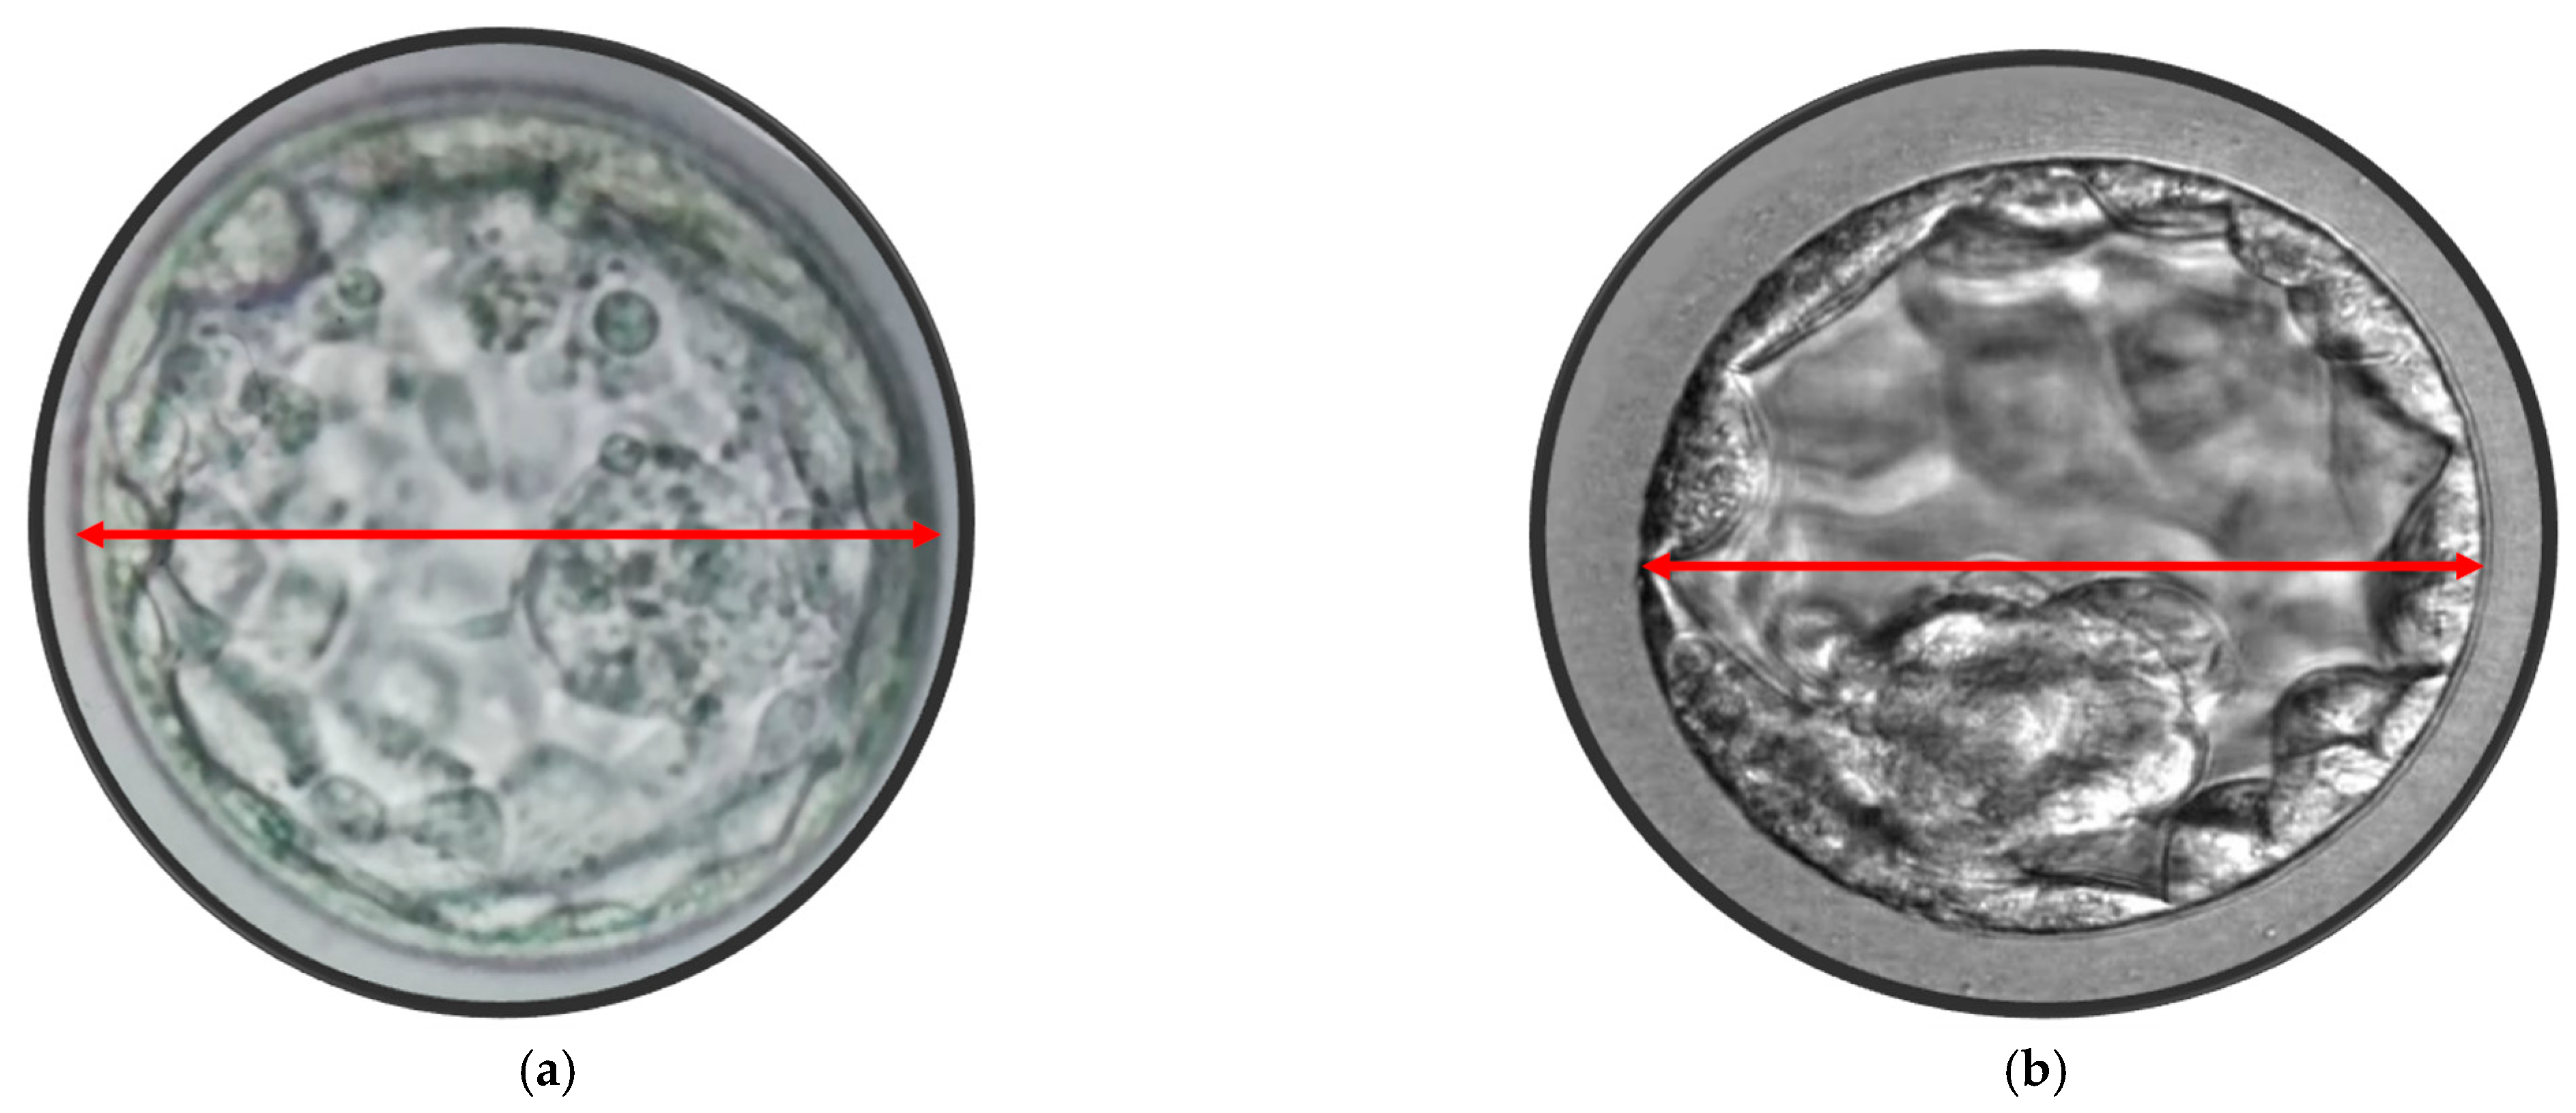

2.3. Blastocyst Morphometric Evaluation